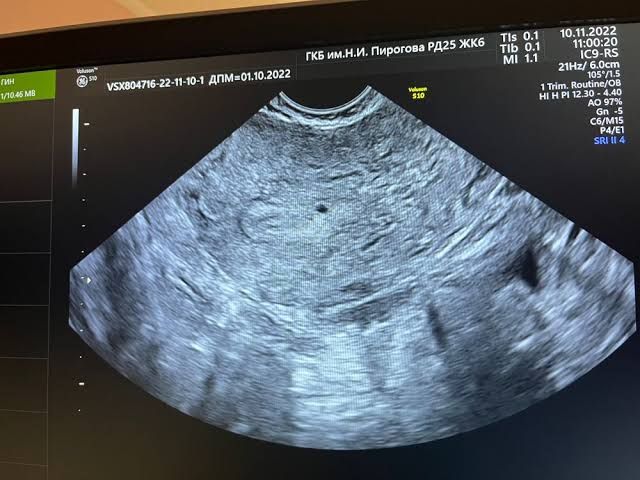

Вот так выглядит на супер раннем сроке, как точечка.